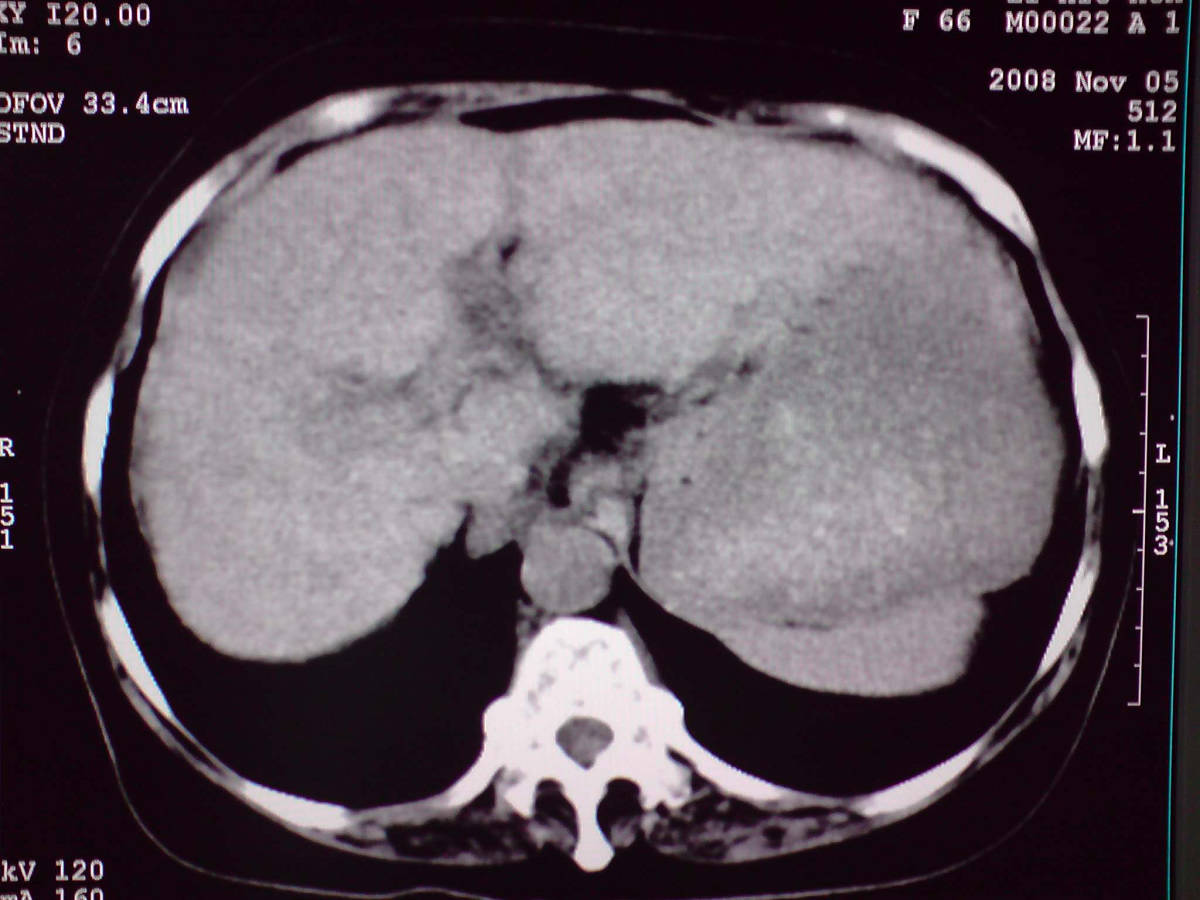

小网膜区见类圆形软组织密度肿块,密度不均,内见不规则低密度区,与肝左叶分界模糊,肝脏体积缩小,密度不均匀,边缘呈波浪状,尾状叶明显增大,脾脏下缘明显超出肝脏下缘。

意见:肝硬化并外生性肝癌,建议增强扫描。

肝脏比例失调,形态失常,外缘呈波浪状,腹腔内肿块内见低密度区并与肝脏界限欠清

考虑外生性肝癌,左肺下叶占位,肝硬化

有肝硬化背景,肝胃间隙见不规则形,且密度不均匀的占位性病变,与肝左叶分界不清,首先考虑外生性肝癌可能性大,不排外肝胃间隙恶性占位肝脏受侵可能性。左肺下叶结节影,其内见空泡征,边缘见毛刺,从一元化的角度首先考虑转移。

1 肝脏各叶比例失调,形态失常,外缘呈波浪状。右叶萎缩,左叶 尾叶增大。2 腹腔内软组织密度肿块,低于肝实质密度,内见低密度区,并与肝脏界限欠清。腹膜后见肿大淋巴结,并与腹腔肿块关系密切。3 左肺下叶肿块,见边缘毛刺征及胸膜凹陷征,并与近肺门侧见异常血管相连。

综合考虑:左下肺周围性肺癌伴腹腔 腹膜后淋巴结转移!另:肝硬化!

1肝胃韧带区域一肿块,肿块上缘与肝左叶相连。肝硬化。考虑肝外生型肝癌可能性大,不除外间质瘤。2左肺下叶背段一结节,有偏心性空洞,长毛刺,其周有多发小结节。考虑结核可能性大。

感谢大家的讨论,今天拿到病理结果是肝细胞癌